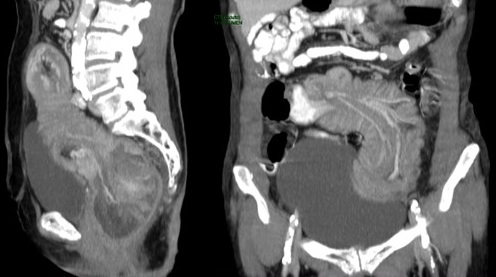

Se presenta el caso de una paciente femenina de 71 años, que ingresa por guardia con dolor abdominal en fosa iliaca derecha y deposiciones diarreicas sanguinolentas. Al examen físico, abdomen blando depresible, con masa palpable, y doloroso a la palpación en FID. En la TC de abdomen y pelvis con contraste oral y EV se observó el pasaje del contraste oral hasta colon derecho. Ángulo derecho descendido de topografía, donde se observa área redondeada de engrosamiento parietal con realce. Distalmente se observa intususcepción, que compromete el resto de colon hasta el recto con ligero realce parietal en dichos segmentos en relación con hiperemia. No se observó dilatación de asas delgadas.

En la TC de abdomen y pelvis con contraste oral y EV se observó el pasaje del contraste oral hasta colon derecho. Ángulo derecho descendido de topografía, donde se observa área redondeada de engrosamiento parietal con realce. Distalmente se observa intususcepción que compromete el resto del colon hasta el recto, con ligero realce parietal en dichos segmentos en relación con hiperemia. No se observa dilatación de asas delgadas.